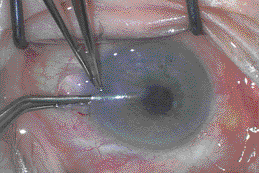

Next, approximately 50% of the air is vented off through the superior

paracentesis. Over the next 24 hours, the grafted endothelium begins to

deturgesce the entire cornea, providing remarkable improvement in vision

overnight (Figure 2). The remainder of the air is rapidly absorbed. Over

the next 4 to 6 weeks, maximum visual quality is attained with retention

of close to the original refractive error of the eye. BCVA appears to be

approximately one to two lines worse than the best potential acuity,

probably because of loss of contrast at the level of the donor-host

interface. However, the benefits of simple surgery in a closed-chamber

environment, rapid visual recovery, minimal spherocylindical change and

a relatively strong, secure globe all outweigh the slight shortfall in

BCVA.

Figure 2. DSEK graft deturgesed 24 hours

after surgery.